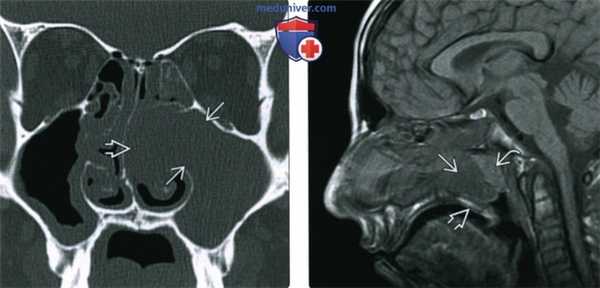

(Слева) При аксиальной МРТ Т2ВИ FS визуализируются гипоинтенсивные полипы, заполняющие решетчатые и основные пазухи и приводящие к их вздутию. На Т2 ВИ гипоинтенсивные полипы имитируют газ в пазухах.

(Справа) При сагиттальной МРТ Т1ВИ С+ у этого же пациента в полости носа визуализируются множественные полипы, накапливающие контраст. Полипы в основной пазухе характеризуются сигналом смешанной интенсивности. Обратите внимание на выраженное истончение кортикального слоя ската.